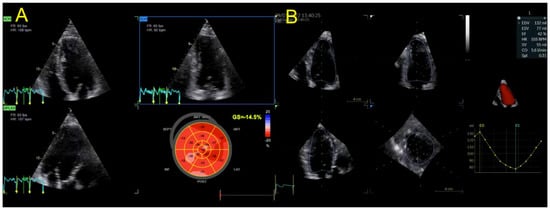

| Echocardiography | Hypokinetic non-dilated cardiomyopathy LVEF = 42% Mild mitral regurgitation IAS aneurysm | Hypokinetic non-dilated cardiomyopathy LVEF = 34% Mild mitral regurgitation IAS aneurysm | Left ventricular concentric hypertrophy LVEF = 54% |

| Cardiac magnetic resonance imaging | Hypokinetic non-dilated cardiomyopathy Left ventricular non-compaction LVEF = 50% | Hypokinetic non-dilated cardiomyopathy Regional sub-epicardial fibrosis LVEF = 41% | Not carried out |